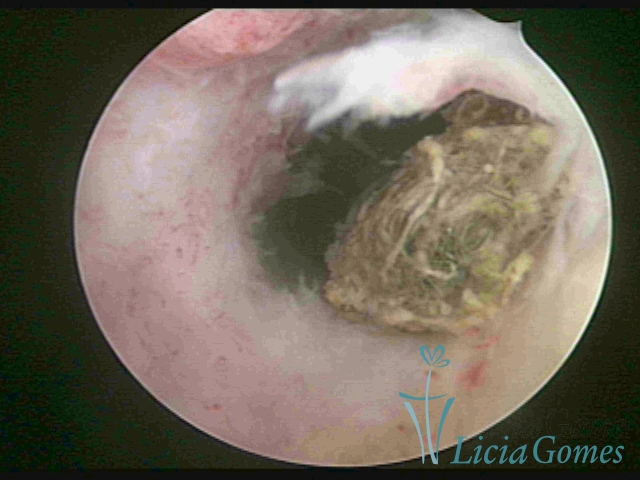

Restos ovulares íntegros em cavidade uterina